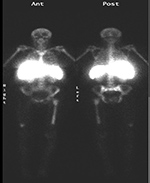

| Figure 35A |

Figure 35B |

| PA Chest radiograph (A) demonstrates a sternal cage. Whole body Tc99m MDP images (B) demonstrate focal radiotracer activity in ribs bilaterally on the anterior view representing the sites of sternal cage fixation with bony reaction. |